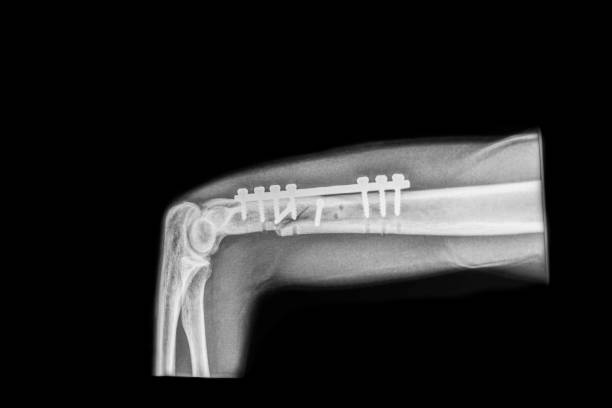

Fracture Repair (Internal Fixation) is a surgical procedure used to treat broken bones, especially when the fracture is complex or unstable. In this procedure, the surgeon uses metal implants such as plates, screws, or rods to hold the broken bone pieces in place while they heal. Internal fixation provides stable support, allowing the bone to heal in the correct position and reducing the need for a cast. This method is commonly used for fractures in areas like the arm, leg, or spine. It improves alignment, accelerates recovery, and reduces the risk of complications like malunion or nonunion. After surgery, physical therapy is often recommended to restore strength and function.

Orthopedic trauma surgery involves the treatment of severe bone fractures, joint injuries, and soft tissue damage caused by accidents or trauma. The goal is to restore function, alleviate pain, and ensure proper healing of bones, muscles, ligaments, and tendons. Common conditions treated include broken bones, dislocations, and complex fractures. Surgical procedures may include internal fixation with plates, screws, rods, or external fixation devices to stabilize the injured area. Rehabilitation and physical therapy are typically needed to restore strength and mobility after surgery. Orthopedic trauma surgery plays a crucial role in helping patients recover from traumatic injuries and return to normal activities.